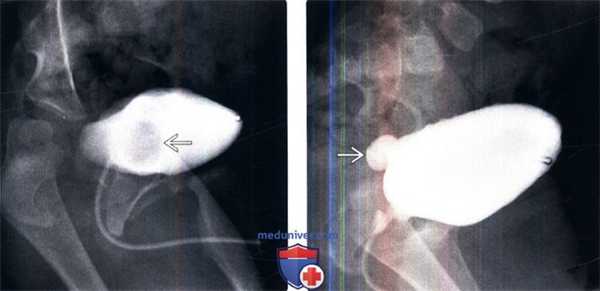

(Слева) МЦУГ в прямой косой проекции: у младенца мужского пола с анамнезом инфекции мочевыделительных путей определяется округлый дефект наполнения мочевого пузыря с гладкой поверхностью. Эти признаки характерны для уретероцеле.

(Справа) После дальнейшего растяжения мочевого пузыря уретероцеле вывернулось наружу из просвета мочевого пузыря. Выворот уретероцеле можно ошибочно принять за дивертикул мочевого пузыря.

(Слева) Экскреторная урография: полное удвоение левых мочеточников с эктопией уретероцеле в области шейки мочевого пузыря. Дефекты наполнения в расширенной части мочеточника представляет из себя кистозный уретерит.

(Справа) КТ с контрастированием, корональный срез: внутрипузырное уретероцеле с cony ствующим расширением мочеточника и чашечек. Гидронефроз встречается относительно редко и обычно не выражен у пациентов с внутрипузырными уретероцеле.